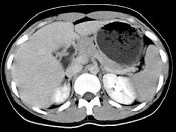

- 单项选择题结合图像,最可能的诊断为 ( )

A、胰腺癌

B、胰岛细胞癌

C、胰腺囊腺癌

D、胰腺炎

E、以上都不是